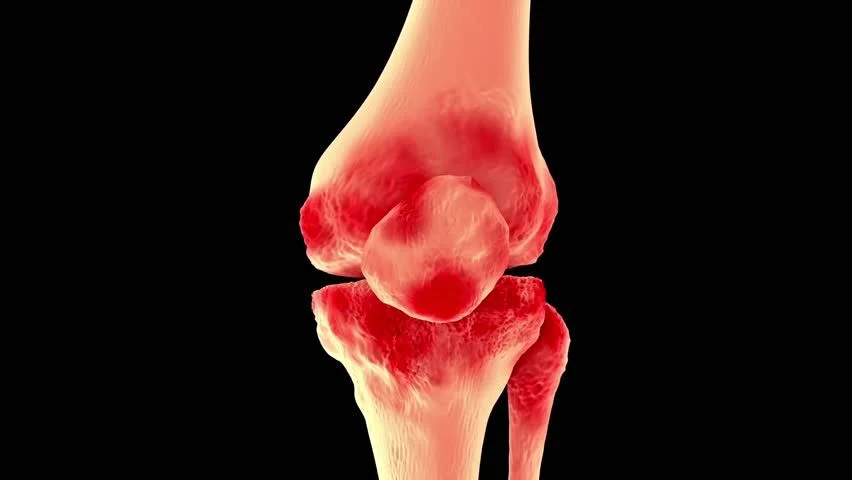

Combate à inflamação, ao inchaço articular e à sensação de “travamento” que muitas pessoas sentem na região da coluna.

Porque ele não trata apenas o sintoma (a dor) — ele ataca a raiz da questão: desgaste da cartilagem, inflamação articular, comprometimento da estrutura que sustenta a coluna. Em vez de usar apenas analgésicos ou anti-inflamatórios que mascaram o problema, o Maxxi-Art 2.0 trabalha para regenerar, apoiar, fortalecer. Isso faz diferença sobretudo na coluna: quando suas articulações estão bem, a coluna inteira “respira” melhor — menos dor, mais movimento, mais liberdade.